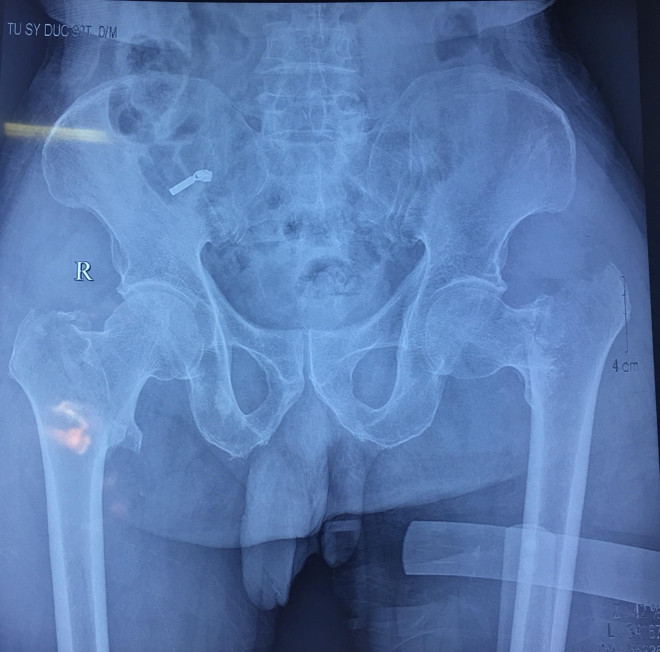

Hy hữu: Phẫu thuật thay khớp háng 2 bên cho cụ ông 92 tuổi ảnh 2Phim chụp X-quang của bệnh nhân. (Ảnh: PV/Vietnam+)

Thay khớp háng cả hai bên đối với bệnh nhân trẻ tuổi đã là một thách thức rất lớn vì đòi hỏi mổ rất nhanh, gây mê hồi sức đảm bảo, trang thiết bị đầy đủ, theo dõi và hồi sức sau phẫu thuật chu đáo và cẩn thận mới đảm bảo an toàn cho người bệnh.

Các bác sỹ đã dùng phương pháp thay khớp háng bán phần không ximăng với kỹ thuật đường mổ nhỏ, ít xâm lấn, vết mổ chỉ từ 4-5cm (đường mổ rất ngắn), gây tê ngoài màng cứng, giảm đau ngoài màng cứng. Người bệnh trong mổ vẫn tỉnh táo, ít đau, giảm thiểu nguy cơ nhiễm trùng, chăm sóc hậu phẫu dễ dàng hơn. Ca phẫu thuật kéo dài trong 1 giờ đồng hồ.